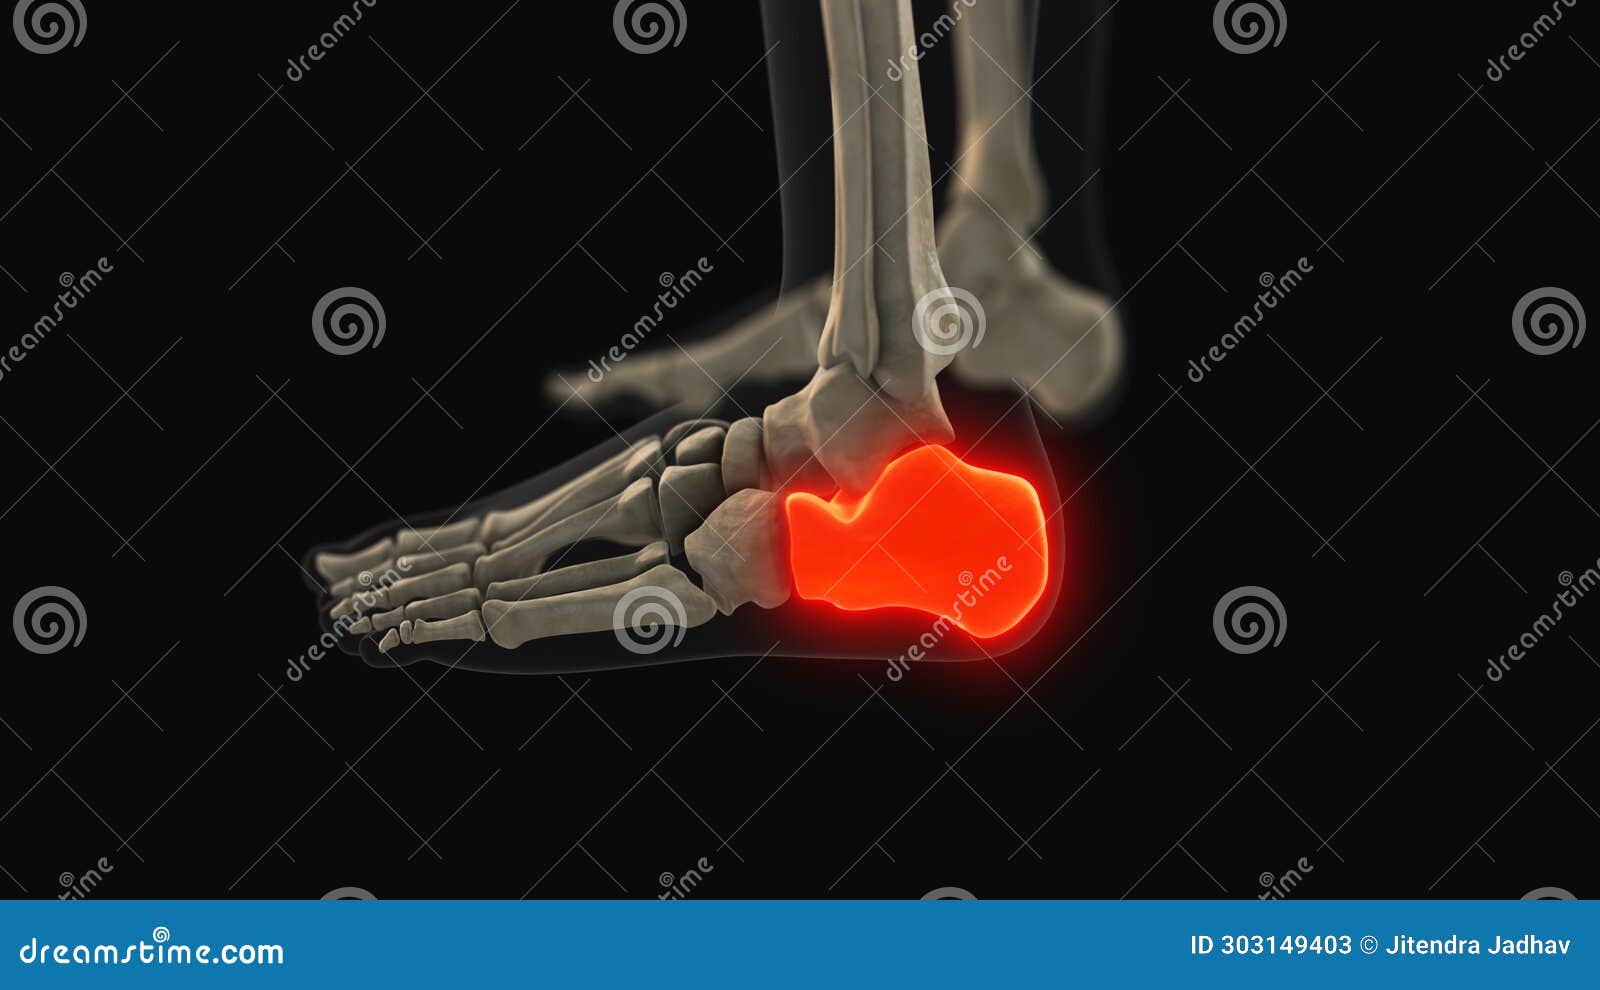

From www.dreamstime.com

Medical Animation of the Calcaneus Bone Pain Stock Image Image of Pain On The Calcaneus Bone Learn about side heel pain causes, symptoms, and treatment options. It is one of the tarsals, the bones that make up part of the foot and ankle. This type of pain is a common complaint for people of all ages and activity. Heel pain causes a throbbing, aching, burning, or stabbing sensation in the back or bottom of the foot.. Pain On The Calcaneus Bone.

Calcaneus Bone Anatomy with Ciculatory System Stock Illustration Pain On The Calcaneus Bone Learn about side heel pain causes, symptoms, and treatment options. Heel pain causes a throbbing, aching, burning, or stabbing sensation in the back or bottom of the foot. The calcaneus is the bone that forms the heel of the foot. It is one of the tarsals, the bones that make up part of the foot and ankle. If the pain. Pain On The Calcaneus Bone.